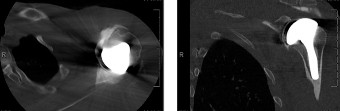

CT arthrograms of the patient’s left shoulder are shown in Figure 2–56. CRP is <3, ESR 45. The patient continues to have pain, so you decide to perform arthroscopic biopsy to obtain tissue cultures. Frozen sections show <5 PMNs per hpf, and Gram stains are all negative.

Figure 2–56

The correct answer is (B). Figure shows contrast under the glenoid component. Given the patient’s normal inflammatory markers and frozen sections combined with continued pain and loosening on CT, infection with P. acnes(an organism that is very difficult to isolate) should be investigated by holding any cultures for at least 2 weeks to see if it will eventually grow. Chocolate agar (Choice C) is mainly used for growing species such as H. influenzae and Neisseria meningitidis not P. acnes. A is incorrect since the patient’s cell count and frozen sections are clearly abnormal, therefore referral to pain clinic would not be appropriate. However, Choice D would be too aggressive an approach given that no organisms have been isolated, frozen sections show <5 PMNs per hpf, and the patient has relatively normal inflammatory markers.